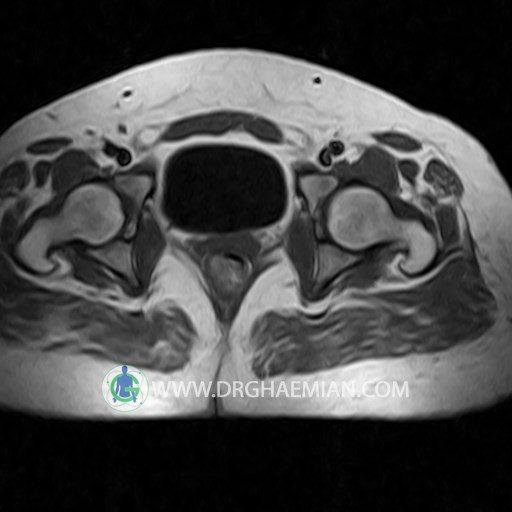

پزشکان اغلب از تصویربرداری ام آر آی برای تشخیص و درمان عارضه های پزشکی که فقط با استفاده از اشعه ایکس یا میدان مغناطیسی و امواج رادیویی قابل مشاهده است، استفاده می کنند. دستگاه ام آر آی تصاویر دقیق از ساختار های داخلی بدن ایجاد می کند. در این کیس کیست بارتولین لگن و تجمع دورمقعدی و کیست ساده ایی در تخمک چپی دیده می شود.

HIP JOINT MRI

( without contrast )

Technique : coronal STIR , coronal T2 , Axial T1 , axial T2 .

REPORT:

The femoral heads and acetabula are normal shape , signal intensity and the femoral heads are well covered by the acetabular margins .

The joint spaces are of normal width without fluid collection .

the articuler surfaces are smooth and congruent and show normal cortical thickness .

there are no marginal osteophytes or subchondral signal changes .

The bone marrow shows normal signal intensity , especially in the femoral head and neck .

Each femoral shaft has normal margins and contains a normal bone marrow signal .

– Simple cyst (28×32mm) in left ovary

– Cyst like lesion (20×25mm) in right vaginal wall suggestive for bartholin cyst and perianal collection

are seen.

COMMENT: Clinical correlation is recommended.